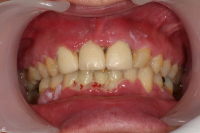

En volymökning av mjukvävnaden kring tänderna som är associerad med intag av läkemedel tillhörande grupperna antiepileptika, immunosuppressiva läkemedel och kalciumblockerare.

Inflammation är den utlösande faktorn som driver tillväxten av mjukvävnaden därför är plackkontroll av största vikt.

Förekomst av gingivala hyperplasier med djupa tandköttsfickor och svåra hygienförhållanden som följd.